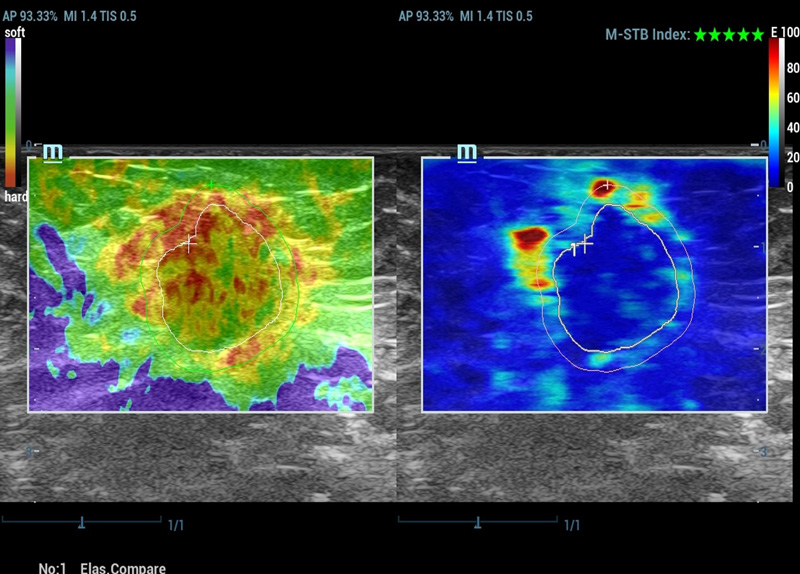

M-Reference E Compare

Strain e share wave insieme per ispirare il futuro

M-Ref. E Compare

M-Ref. E Compare tumore maligno al seno

M-Ref. E Compare supporta la visualizzazione dell'elastografia strain in tempo reale e della STE in un unico piano per la valutazione della rigiditĂ dei tessuti.